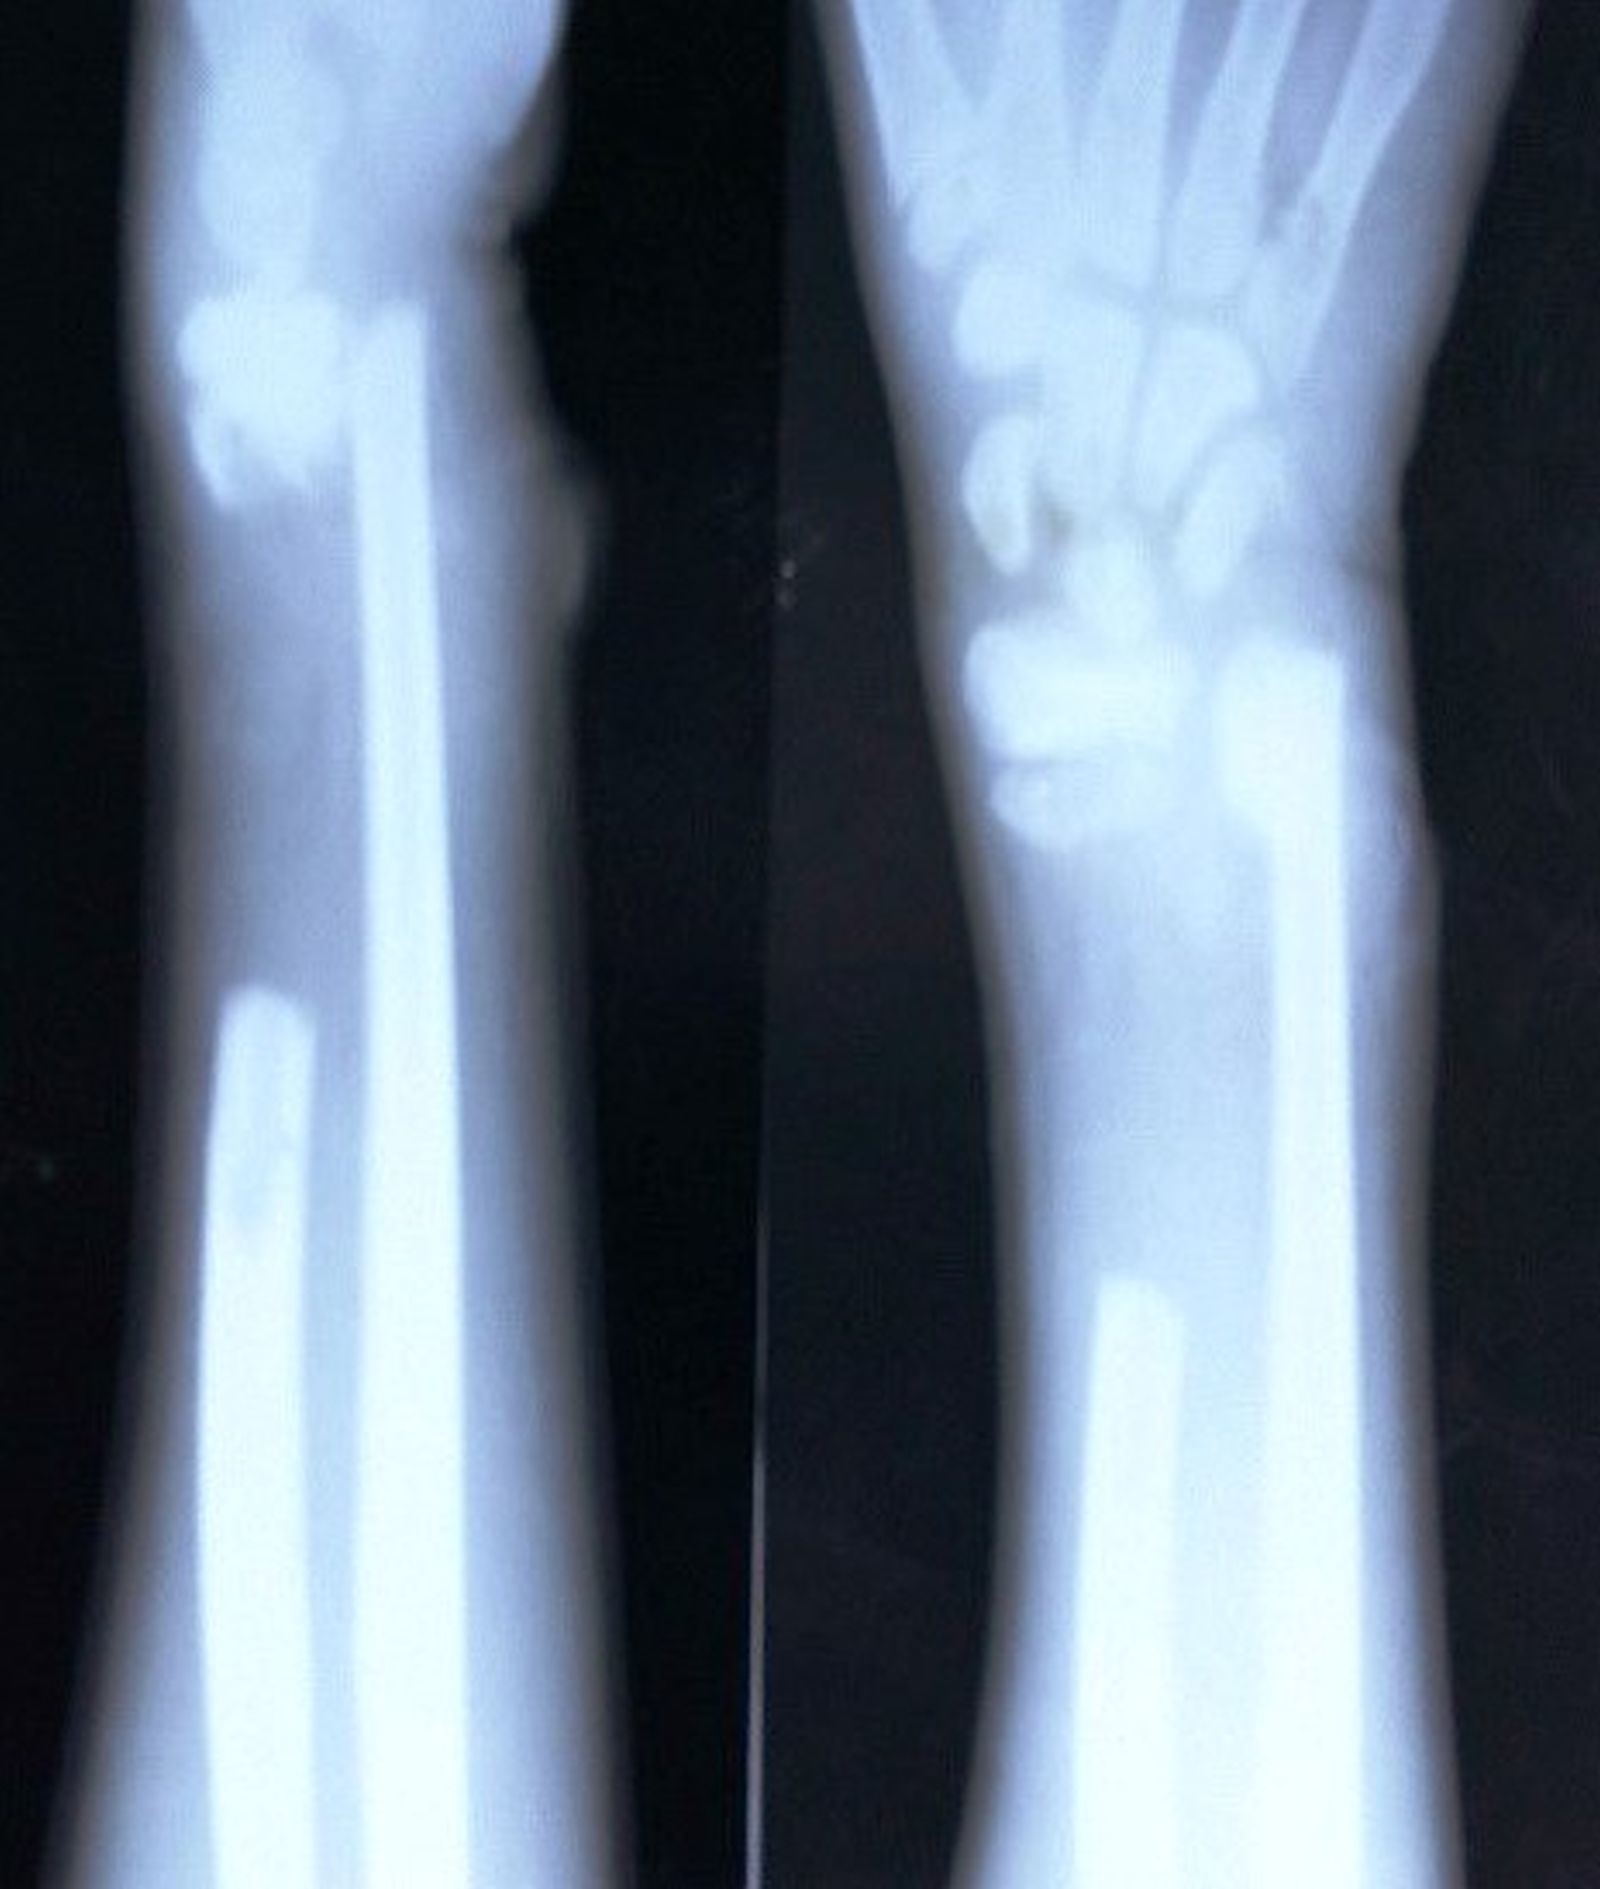

XRay wrist fracture. Download Scientific Diagram Spontaneous Wrist Fracture Spontaneous fracture occurs primarily in two. A broken wrist, or wrist fracture, is a common injury that can affect any of the 10 bones that make up your forearm and wrist. This type of fracture occurs most often after a fall onto an outstretched hand. In fact, the radius is. Wrist fractures present specific symptoms such as severe pain, loss. Spontaneous Wrist Fracture.

Cureus Spontaneous Bone Regeneration in an Open Segmental Fracture of

Cureus Spontaneous Bone Regeneration in an Open Segmental Fracture of Spontaneous Wrist Fracture In fact, the radius is. Distal radius fractures are very common. A fracture of the distal radius occurs when the radius — one of the two long bones in the forearm — breaks close to the wrist. Wrist fractures present specific symptoms such as severe pain, loss of mobility in the hand or wrist, deformity in appearance, and tingling or.. Spontaneous Wrist Fracture.